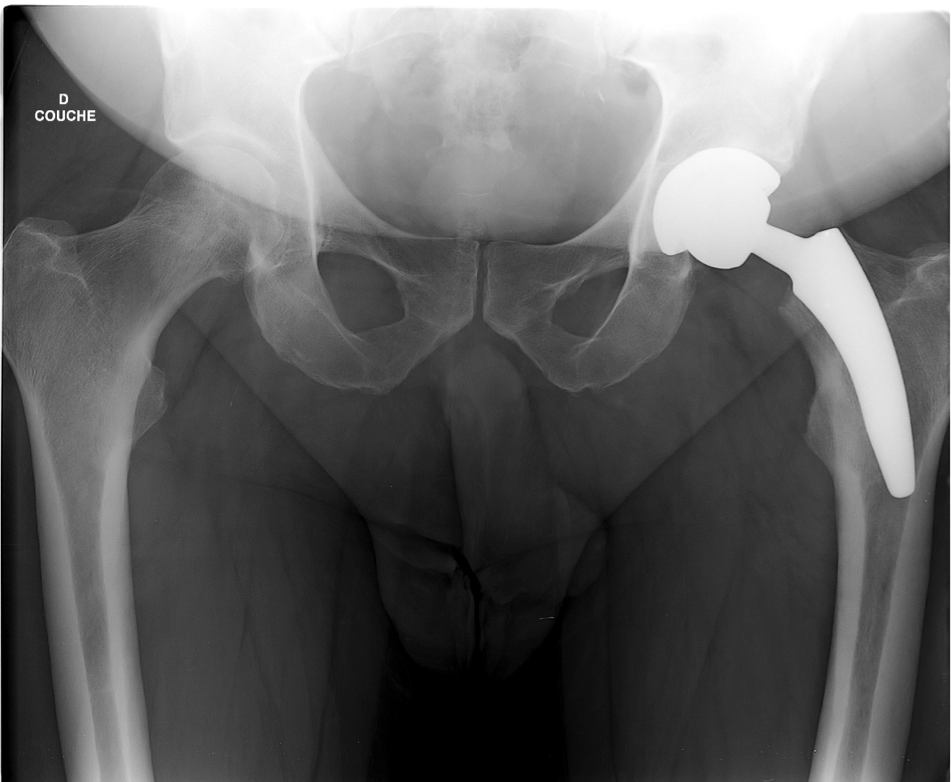

One-piece femoral stems pose different problems in reproducing the morphology of these vara hips, even though their use appears to be safer. Massin et al [8] have shown that with a set of 15 implant sizes, with 3 different metaphyseal configurations and 2 neck-shaft angle options, offset could be restored at the planning level in 86% of cases. However, the stock of implants required is very large and not in line with the current trend of cost optimization. In addition, there are still 14% of hips that do not have an anatomical reconstruction. Finally, this is only based on planning data and has not been proven in practice. In addition, the use of pins with increased femoral offset has frequently resulted in reduced arthroplasty survival compared to the same standard implants due to excessive stress on the femoral fixation. For example, we have found that femoral implants with varied necks (Lubinus SP2 117°) reproduce the anatomy of coxa vara hips better than standard implants, but are more prone to femoral loosening (7% at 6 years' follow-up, Fig. 3) and do not prevent dislocation (5.4%) [9].

This allows the stem to be positioned in varus with greater support on the calcar. It is therefore often necessary to use a smaller implant than planned. The importance of planning is paramount because the height of the neck cut will induce a valgus or varus positioning of the implant. While this can be considered for moderate femoral deformities (+ or - 10° of a normal CC'D angle and + or - 5 mm of a normal offset (30-40 mm)), it can be problematic for major anatomical anomalies. Implanting a short stem on a hip with a long neck coxa vara will result in the positioning of a small short stem in a large vara (Figs. 6 and 7).

The risk of 3-point fixation is increased. The physiological transmission of stresses seems to be disturbed by this stem, which has a predominantly cervical anchorage. The increase in varus stresses on a small, short stem may reduce the durability of fixation by tilting the implant. There is no long-term series of short stems implanted on long-neck coxa vara. In the present state of knowledge, it seems reasonable to restrict the use of short stems to coxarthroses on hips with a relatively standard anatomy, and not to implant them on extreme deformities, so as not to compromise their development.